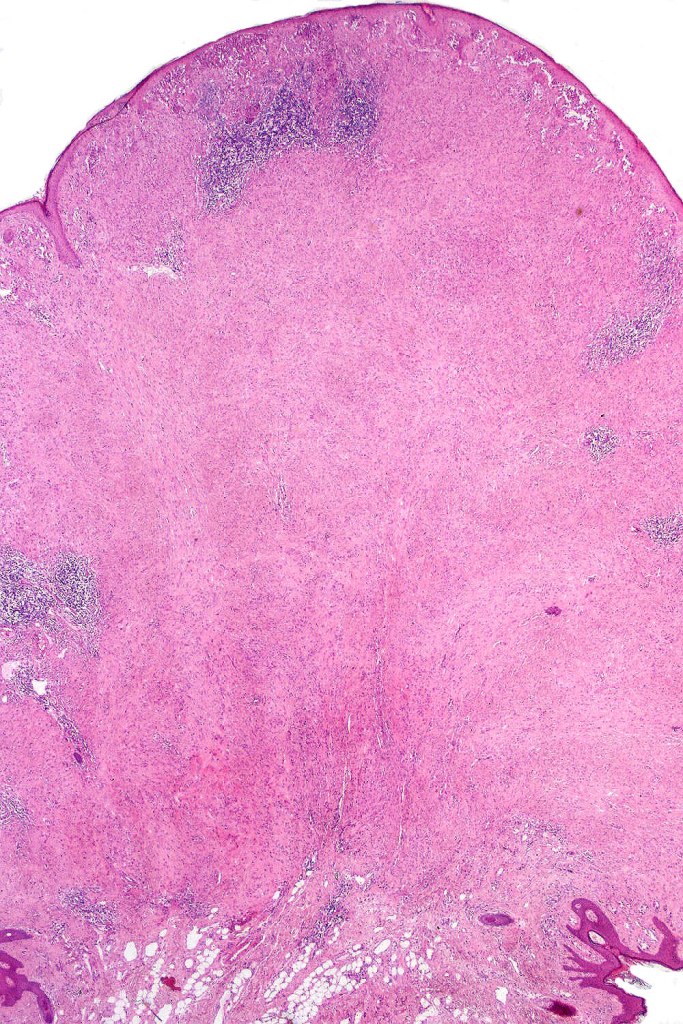

•Sharply circumscribed (begins and ends with a nest), symmetrical dome-shaped lesion. Symmetry is both horizontal and vertical (see image below)

•Wedge-shaped with the base uppermost or sometimes plaque-shaped silhouette

•Matures with depth-often best recognized at scanning/low power magnification & readily confirmed with S100 or MART1

•Maturation implies nest size and cell size diminishing with depth, at the base, the infiltrate may have a single cell infiltrating pattern

•Lymphocytic infiltration at the base of the lesion